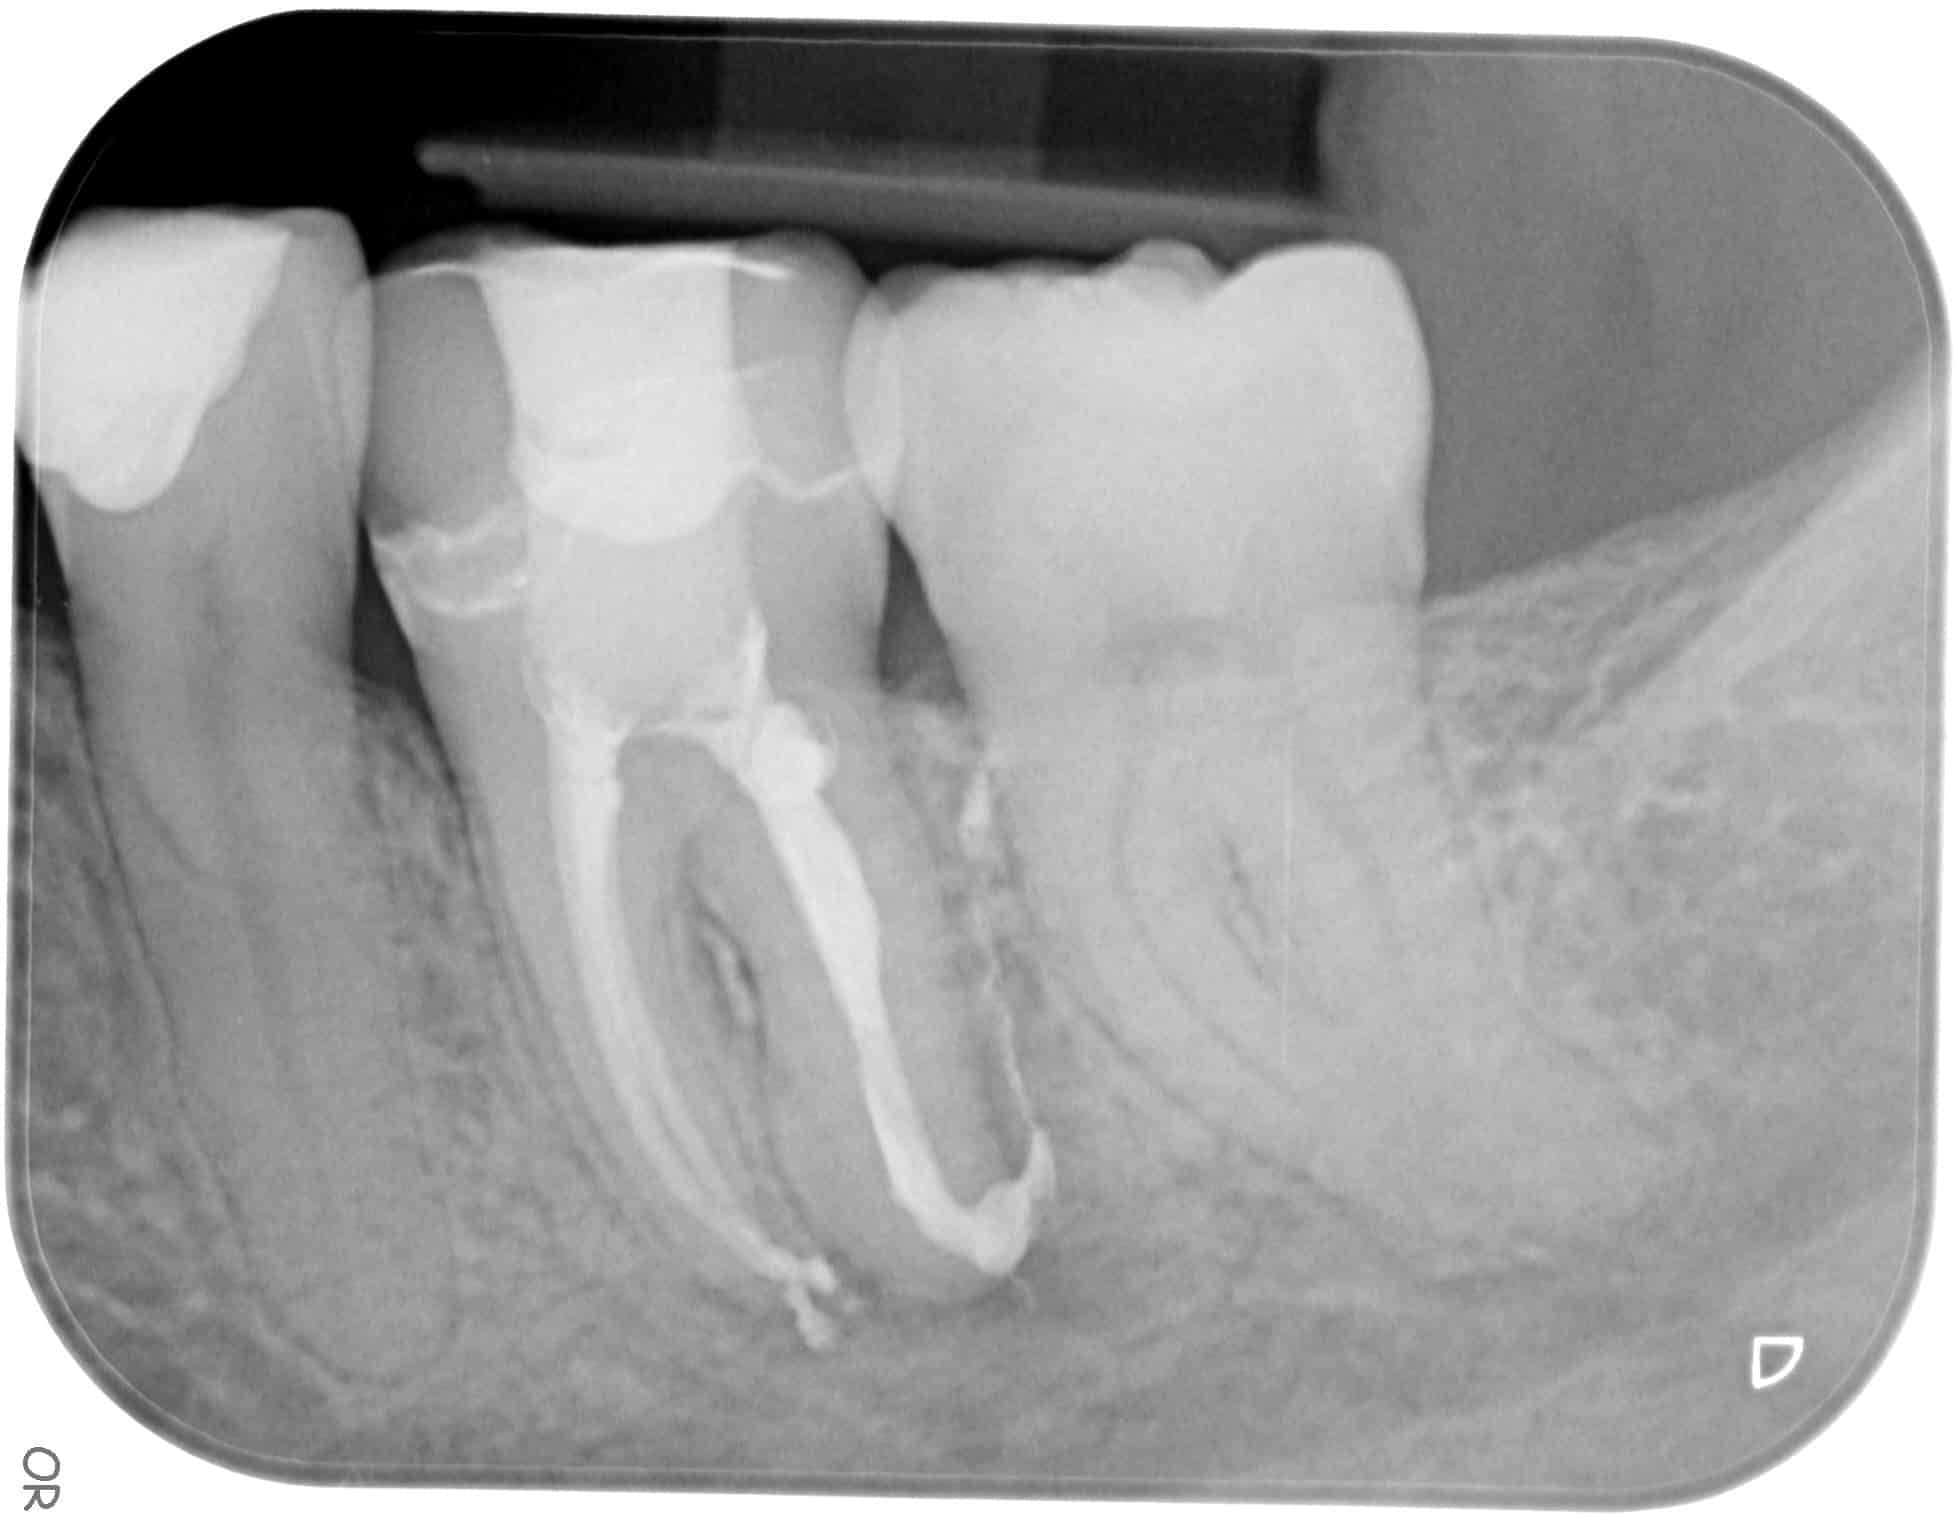

Root canal treatment is carried out when the the nerve in your tooth is infected. It involves cleaning out the nerve and filling it up so that we can save your tooth.

We recommend having a crown on the tooth after your root canal treatment is completed to help protect it and reduce the risk of the tooth fracturing in the future.